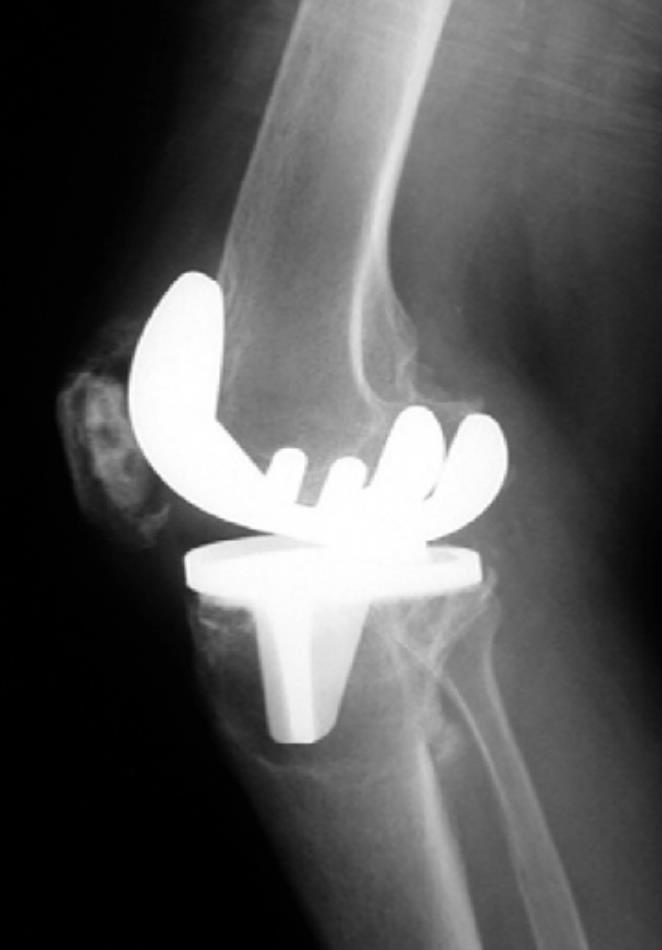

From www.researchgate.net

Aseptic loosening and implant failure in a patient with TKA. A, B Aseptic Loosening Dental Implant Demonstrated in an epidemiological study. In medicine, an aseptic environment is necessary and expected to. This osteolytic effect could be enhanced by vitamin d deficiency, since maier et al. The most commonly occurring mechanical complication is abutment screw loosening, since it is the weakest part of the implant. Asepsis is described as a state free from microorganisms. Moreover, implant surface. Aseptic Loosening Dental Implant.